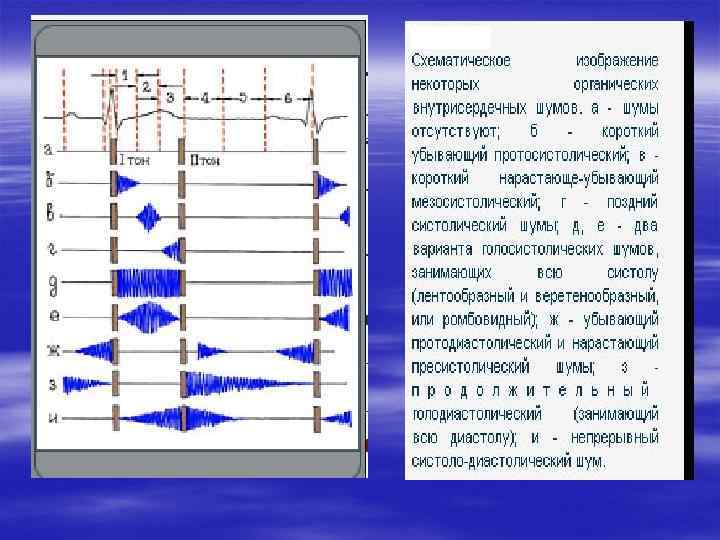

Характеристики шумов сердца § Отношение шума к фазам сердечной деятельности (систолический, диастолический) § Обл. максимального выслушивания § Проведение шума § Тембр, громкость шума, § Форма шума

Характеристики шумов сердца § Отношение шума к фазам сердечной деятельности (систолический, диастолический) § Обл. максимального выслушивания § Проведение шума § Тембр, громкость шума, § Форма шума

Органические диастолические шумы § 1. протодиастолические, возникающие в начале диастолы, сразу после 2 тона; § 2. мезодиастолические, выслушиваемые в середину диастолы; § 3. пресистолические, появляющиеся в конце диастолы перед 1 тоном.

Органические диастолические шумы § 1. протодиастолические, возникающие в начале диастолы, сразу после 2 тона; § 2. мезодиастолические, выслушиваемые в середину диастолы; § 3. пресистолические, появляющиеся в конце диастолы перед 1 тоном.